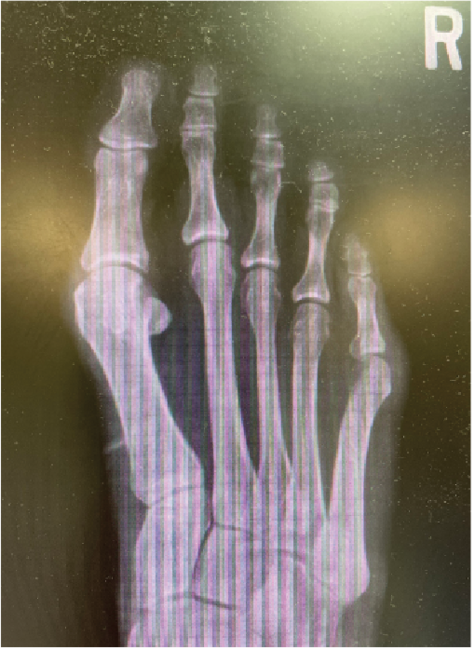

The Bio-Integrative OSSIOfiber Trimmable Fixation Nail (OSSIO) was made to be as rigid as a screw, trimmable to be flush with the bone, and offer a form of compression unlike a screw but just as stable in my hands. What was more the nail needed to require very few steps to place. Place a pin, drill over the pin, and place the nail. The nail could be placed and trimmed flush if only one cortex was drilled or it could be measured like a screw, trimmed, and inserted according to the right length for bicortical fixation options.